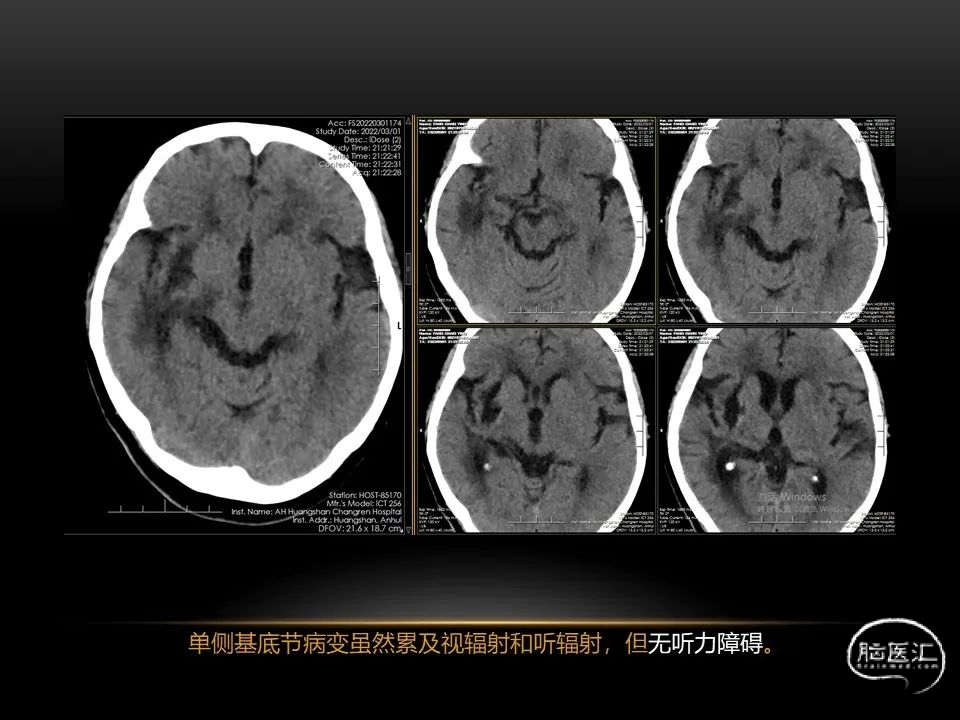

自发性脑出血不仅仅累及内囊后肢才会出现偏瘫及偏身感觉障碍,病变累及大脑脚或辐射冠同样有可能有类似症状和体征。内囊、辐射冠、大脑脚等结构之间是延续的,只是不同区域不同名称而已。定位诊断需要对解剖结构概念清晰,读片准确辨认,灵活掌握。